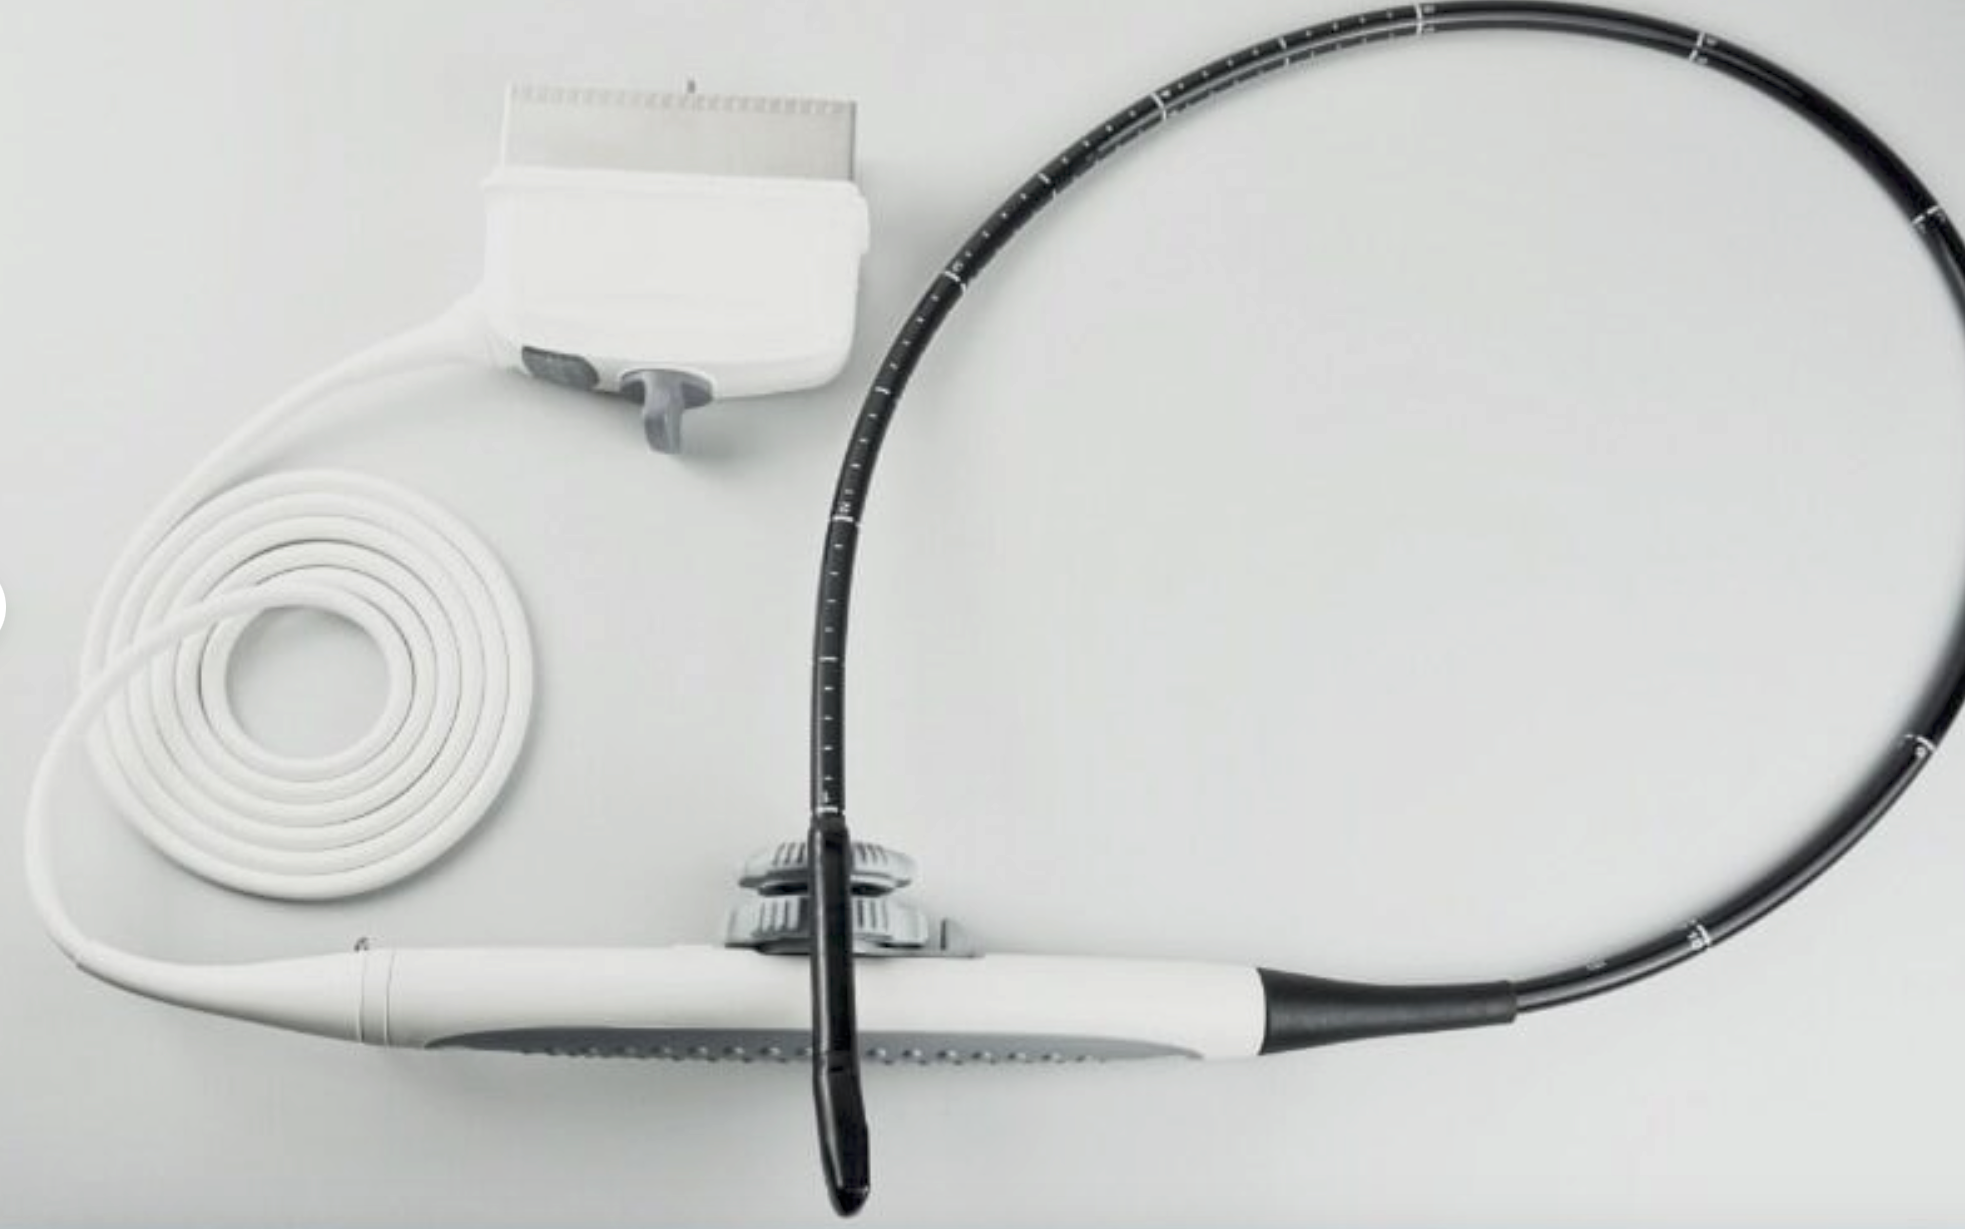

Acuson L538 Linear Array Ultrasound Probe

Sale price$ 246.00